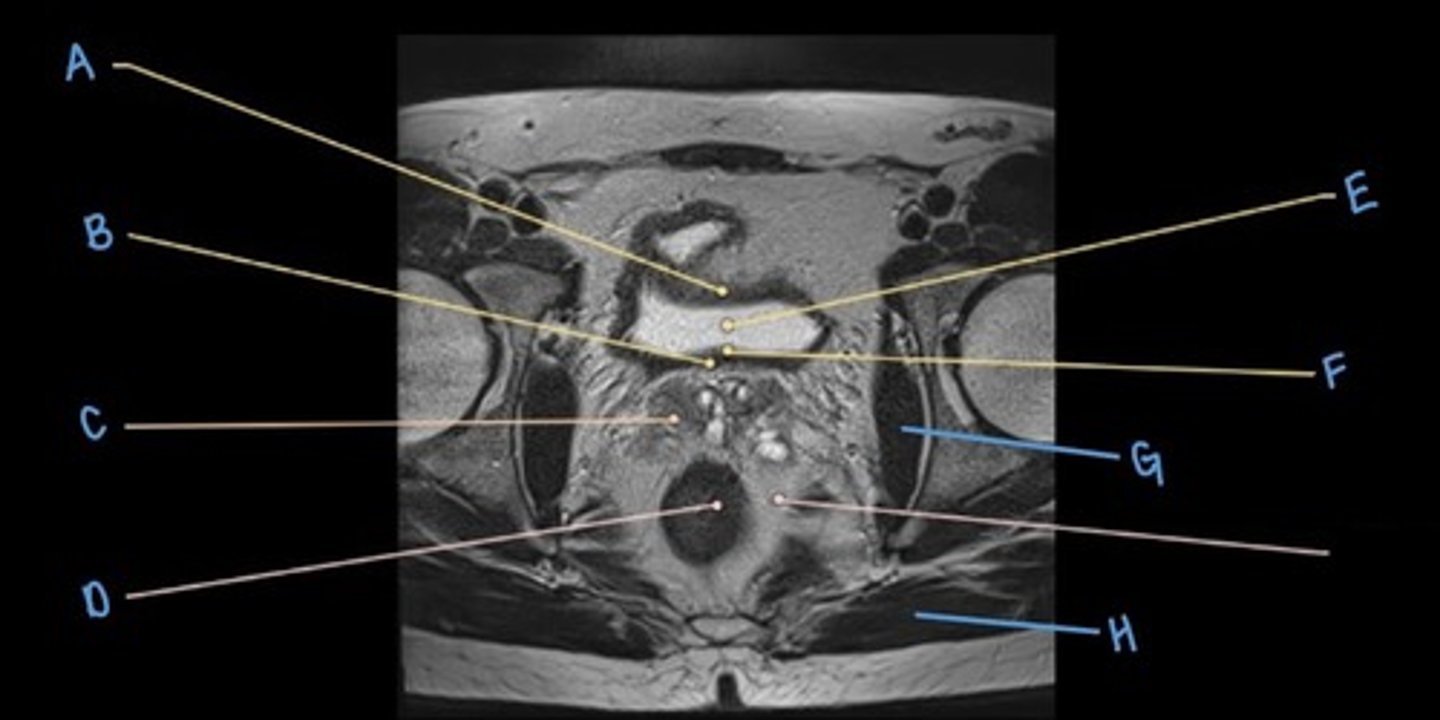

sigmoid colon

A

seminal vesicles

B

prostate

C

rectum

D

pubic symphysis

E

retro-pubic space

F

bladder

G